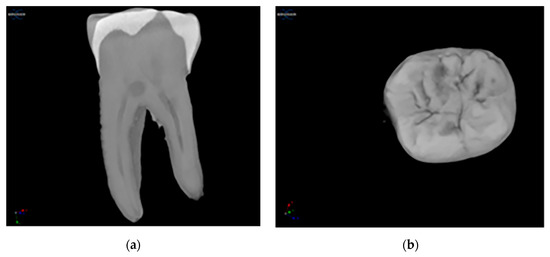

In Figure 5, the STL images obtained by micro-CT pre- and post-instrumentation were presented to all groups in the study, as well as the images obtained by superimposing these images.

Figure 5.

STL images of the micro-CT scans, before (gray) and after canal preparation (pink) and with superimposed STLs. (a) TAC-OR; (b) superimposed on TAC-OR; (c) TAC-PU; (d) superimposed on TAC-PU; (e) CAC-OR, (f) superimposed on CAC-OR, (g) CAC-PU, (h) superimposed on CAC-PU.